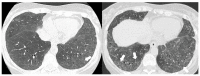

Polymyositis and dermatomyositis are autoimmune idiopathic systemic inflammatory diseases, characterized by various degrees of muscle inflammation and typical cutaneous lesions-the latter found in dermatomyositis. The underlying pathogenesis is characterized by a high level of uncertainty, and recent studies suggest diseases may have different immunopathological mechanisms. In polymyositis, components of the cellular immune system are involved, whereas in dermatomyositis, the pathogenesis is mainly mediated by the humoral immune response. The interstitial lung disease occurs in one-third of polymyositis and dermatomyositis patients associated with worse outcomes, showing an estimated excess mortality rate of around 40%. Lung involvement may also appear, such as a complication of muscle weakness, mainly represented by aspiration pneumonia or respiratory insufficiency. The clinical picture is characterized, in most cases, by progressive dyspnea and non-productive cough. In some cases, hemoptysis and chest pain are found. Onset can be acute, sub-acute, or chronic. Pulmonary involvement could be assessed by High Resolution Computed Tomography (HRCT), which may identify early manifestations of diseases. Moreover, Computed Tomography (CT) appearances can be highly variable depending on the positivity of myositis-specific autoantibodies. The most common pathological patterns include fibrotic and cellular nonspecific interstitial pneumonia or organizing pneumonia; major findings observed on HRCT images are represented by consolidations, ground-glass opacities, and reticulations. Other findings include honeycombing, subpleural bands, and traction bronchiectasis. In patients having Anti-ARS Abs, HRCT features may develop with consolidations, ground glass opacities (GGOs), and reticular opacities in the peripheral portions; nonspecific interstitial pneumonia or nonspecific interstitial pneumonia mixed with organizing pneumonia have been reported as the most frequently encountered patterns. In patients with anti-MDA5 Abs, mixed or unclassifiable patterns are frequently observed at imaging. HRCT is a sensitive method that allows one not only to identify disease, but also to monitor the effectiveness of treatment and detect disease progression and/or complications; however, radiological findings are not specific. Therefore, aim of this pictorial essay is to describe clinical and radiological features of interstitial lung diseases associated with polymyositis and dermatomyositis, emphasizing the concept that gold standard for diagnosis and classification-should be based on a multidisciplinary approach.